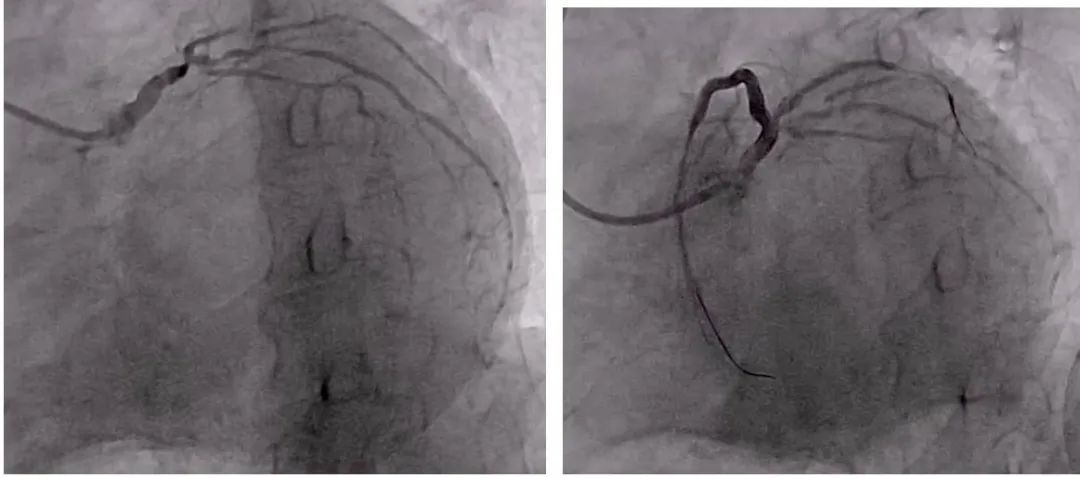

然而,当冠状动脉造影完成后,医务人员一度陷入沉默。因为3年来一直没有进行干预与治疗,现在陈叔的病情十分严重:心脏冠状动脉的左主干末端重度狭窄,前降支开口慢性完全闭塞,中间支、回旋支存在重度狭窄和严重钙化。这样的情况,正是陈叔命悬一线的原因。

心脏重症科负责人靳文、主治医师陈武奇沉着冷静,使用多种生命支持药物,及时给予溶栓、止痛,经过反复多次尝试,最终顺利开通了慢性闭塞的严重狭窄病变血管。术前病变严重的冠状动脉病变,恢复了清晰的正常结构、顺畅的血流和充分的血流量。

文章插图

术前术后冠脉造影对比